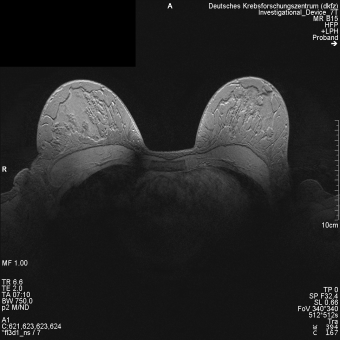

DKFZ Heidelberg, Germany: In vivo images of a healthy volunteer obtained with the 4 channel breast array using a fl3d1_ns sequence (left) and a tse2d1 sequence (right).